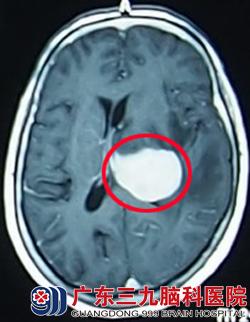

66岁的王女士因反复头晕1个月,在当地检查怀疑为脑肿瘤,为求进一步治疗而来到广东三九脑科医院。入院结合头部检查考虑为左侧基底节丘脑肿瘤(考虑为淋巴瘤可能性大),完善相关检查后在全麻下行左侧基底节、丘脑肿瘤穿刺活检术,术中冰冻病理考虑恶性肿瘤,淋巴瘤可能性大。术后王女士呈嗜睡状态,精神较差、烦躁,考虑为肿瘤进展快速所致,在与家属充分沟通告知病情后,果断为其行抢救性放疗以改善症状,避免病情恶化。放疗2次后王女士精神状态好转,烦躁情况较前改善。抢救性放疗3天后病理回报为弥漫大B细胞淋巴瘤,诊断明确,治疗予同步放化疗,随后行全脑放疗、适形放疗。治疗完毕后王女士各项生命体征平稳,神志清楚,无其他不适症状。治疗后一个月回院复查见其康复良好。

放疗前 放疗后1个月复查肿瘤消失